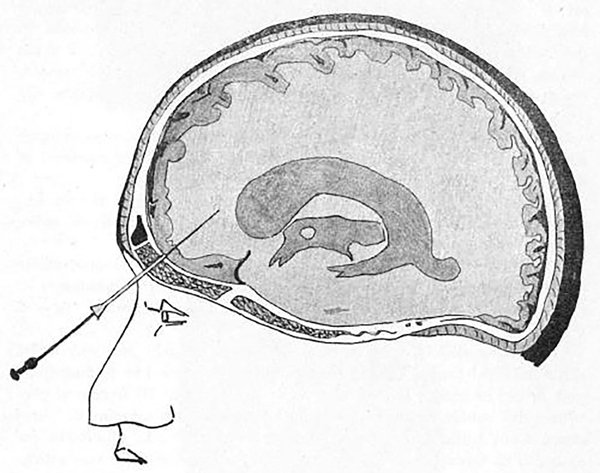

La otra vía, transorbitaria, es poco utilizada y a veces hasta desconocida, a pesar de ser más sencilla y veloz. Fue descripta por Achille Dogliotti1 en 1933 como una variante para la inyección diagnóstica de aire (neumoventriculografía) (Figura 1).

Figura 1: Descripción original de la neumoventriculografía por vía transorbitaria en un paciente portador de hidrocefalia.1 Se aprecia el ventrículo lateral contrastado por aire y la punta de la aguja en el cuerno frontal.